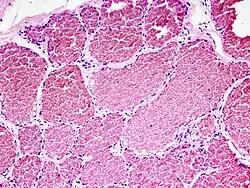

Micro: Necrosis of the media with calcifications, detritus, foam cells (macrophages which have accumulated lipids) and cholesterol clefts, fibrosis of the intima. Thickening of the arterial wall with stenosis.

Gross: Fatty streaks, calcification, ulceration, thrombotic material.